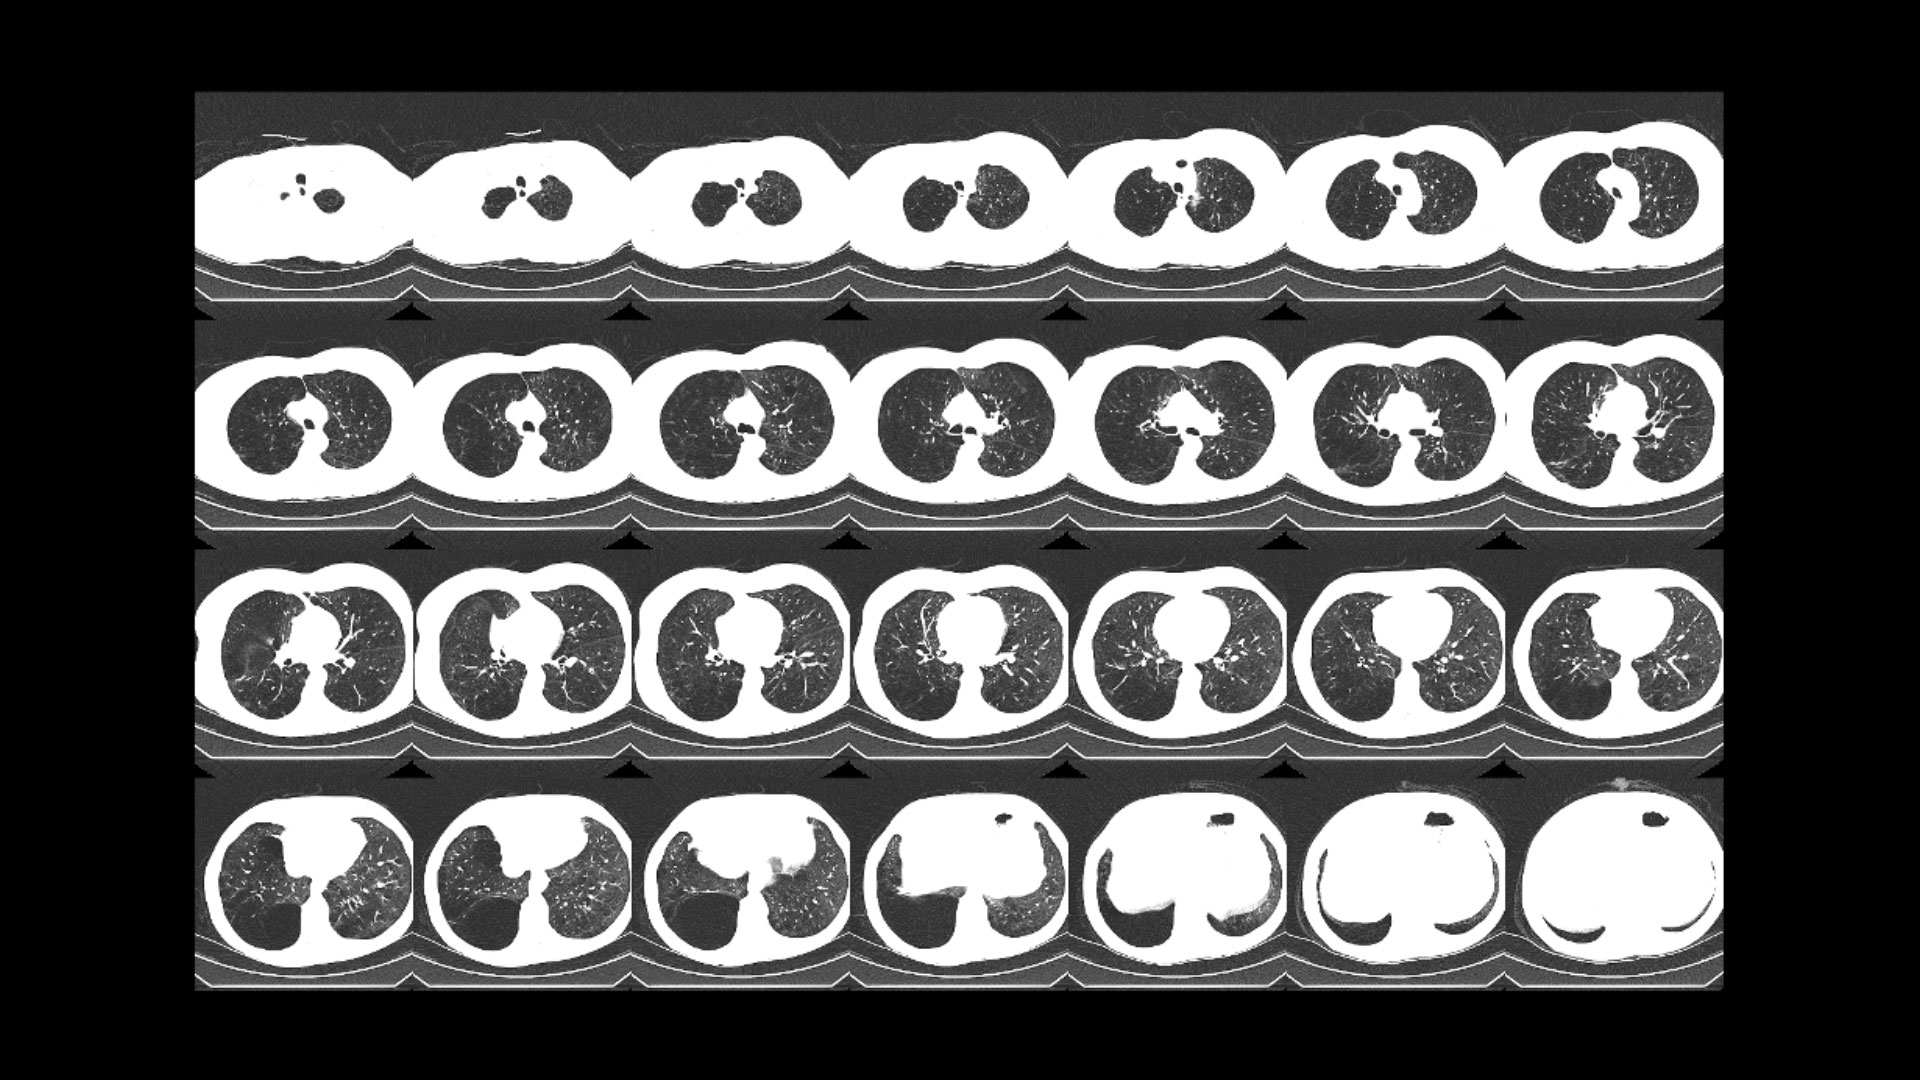

ASiR-V reconstruction using lower dose (up to 82% relative to FBP¹⁰)

This next-level iterative ASiR allows you to lower noise up to 91% at the same dose¹⁰ᵇ and improve spatial resolution up to 2.07X (107%) at the same image noise.¹⁰ᵇ

ASiR-V-feature02-desktop